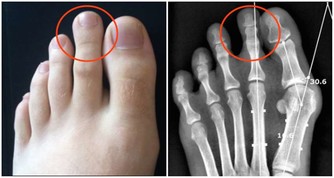

3.膝窩

在膝窩的中點有一個主要穴道叫委中穴,走膀胱經。

膀胱經是人體最大的排毒祛濕的通道,而委中穴是這條通道上的“排污口”。

操作方法:用力敲打5-10分鐘,直到瘀斑、痧點等病理反應物顯出。

1-2週敲打一次,身體就會經過自我排毒的方法來消除這些毒素和廢物。